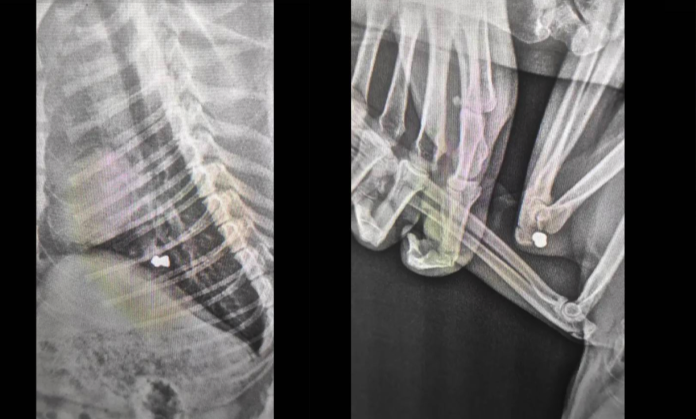

У Магалі, 8 квітня, місцевий житель вистірилв з дробової рушниці в стерилізовану собаку, на клініці рентген показав 9 куль у тілі собаки.

"На рентгені лікарі побачили близько 9 куль 4 з них в легенях. Інші в різних місцях: від задньої лапки — до щелепи. Тобто нелюд стріляв з дробової рушниці.

Ветеренари витягнули ті кулі, які можна було та надали необхідну допомогу. Але 4 кулі в легенях так і залишилися, - зазначають волонтери.